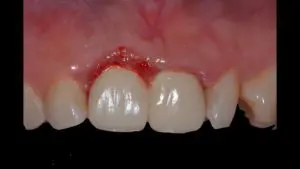

植牙是透過手術,將鈦金屬合金植體植入進齒槽骨中,以達模仿真牙的效果。特色是穩固強度比假牙好,咬合力可恢復到類似真牙的效果。如果是單顆牙齒的治療,不需磨損旁邊的牙齒,只針對手術範圍的牙齒施術,可保持其他真牙的健康。